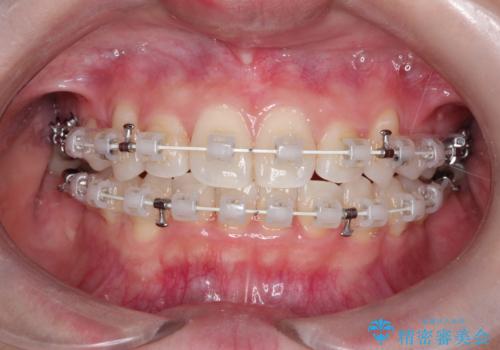

ワイヤー矯正を用いて、欠損部の閉鎖を目的とした後方からの歯の挺出・移動を行いました。

特に、親知らずを活用し、奥歯の噛み合わせを構築することに重点を置きました。